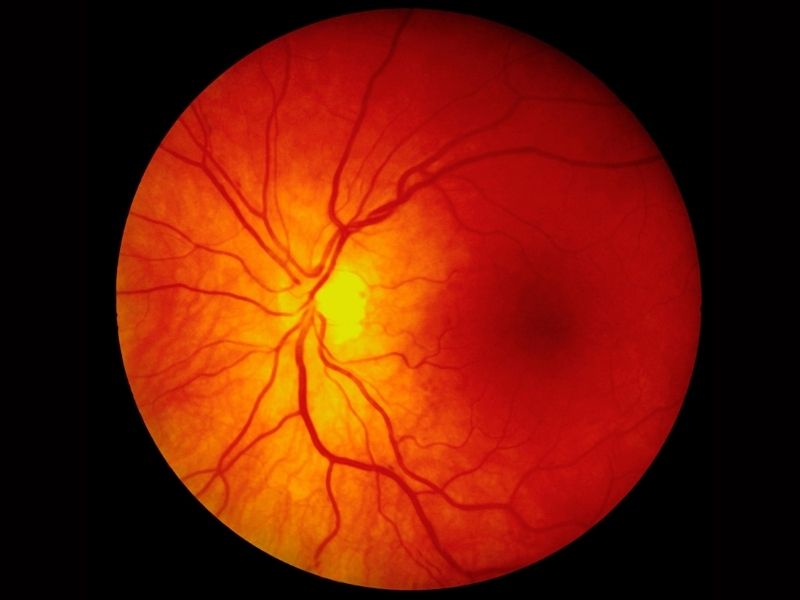

Retina

Işık, vitreustan geçtikten sonra göz kürenin içini kaplayan sinir tabakasına yani retinaya gelir. Retina kameradaki film gibidir. Gelen ışık fotoreseptör tabakada elektrik sinyallerine dönüştürülür. Çomakları içeren fotoreseptörler loş ışıkta görmemizi sağlarken, konları içerenler keskin ve renkli görmemizi sağlarlar. Retinanın merkezindeki bölgeye makula denir. Makulada çok yüksek oranda konları içeren fotoreseptörler olduğundan, keskin ve renkli görmemizi sağlar. Yaşa bağlı makula dejenerasyonu yani ‘sarı nokta’ hastalığı bu bölgeyi tutarak merkezi görmeyi tahrip eder.

Görme Siniri

Retinada oluşan elektrik sinyalleri görme siniri ile beyne taşınır ve beyinde görsel imajlara çevrilir. Görme siniri yaklaşık 1 milyon sinir lifini içerir. Glokomda, göz içi basınç artışına bağlı olarak görme siniri zarar görür.